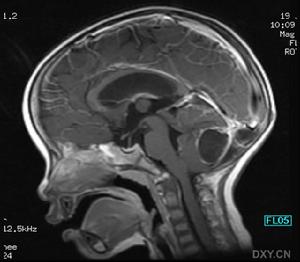

腦CT酒精中毒性神經疾病的中樞神經抑制症狀,應注意與引起昏迷的疾病相鑑別,如鎮靜催眠藥中毒、一氧化碳中毒腦卒中、顱腦外傷等戒斷綜合徵的精神症狀和癲癇發作,應與精神病、癲癇、窒息性氣體中毒低血糖征等相鑑別慢性酒精中毒的智慧型障礙和人格改變,應與其他原因引起的痴呆鑑別。

其它輔助檢查:1.心電圖、腦電圖、腦CT或MRI檢查,有鑑別診斷及中毒程度評估意義;2.肌電圖和神經電生理檢查有鑑別診斷意義。